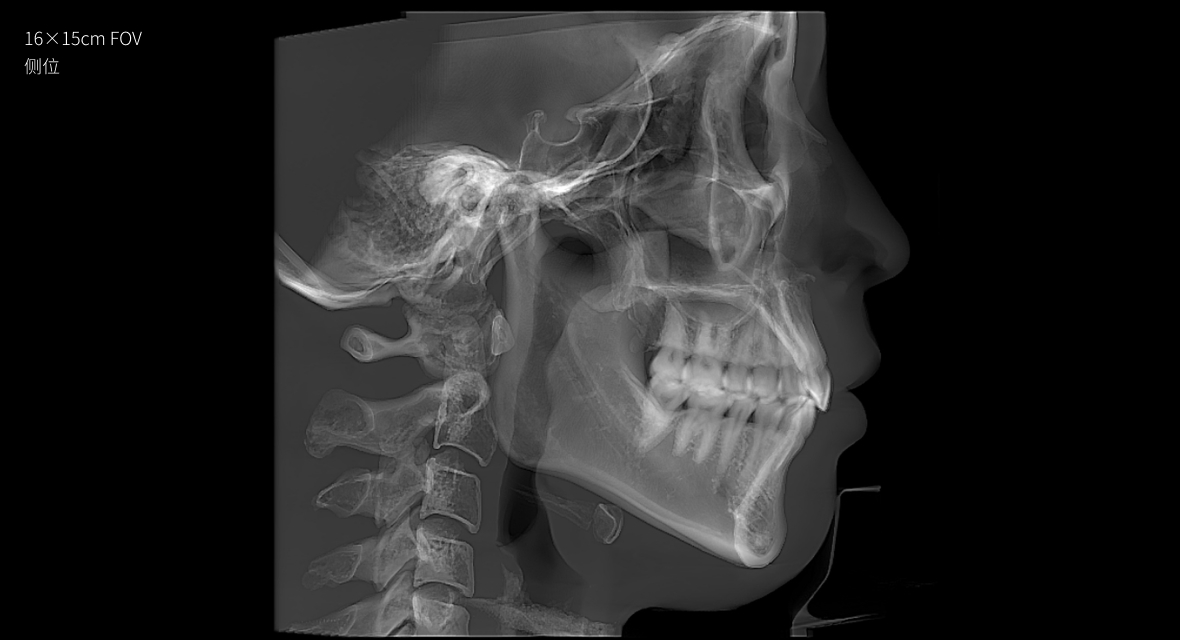

• 3D 正侧位

3D 正侧位

16×15cm

非拼接大视野